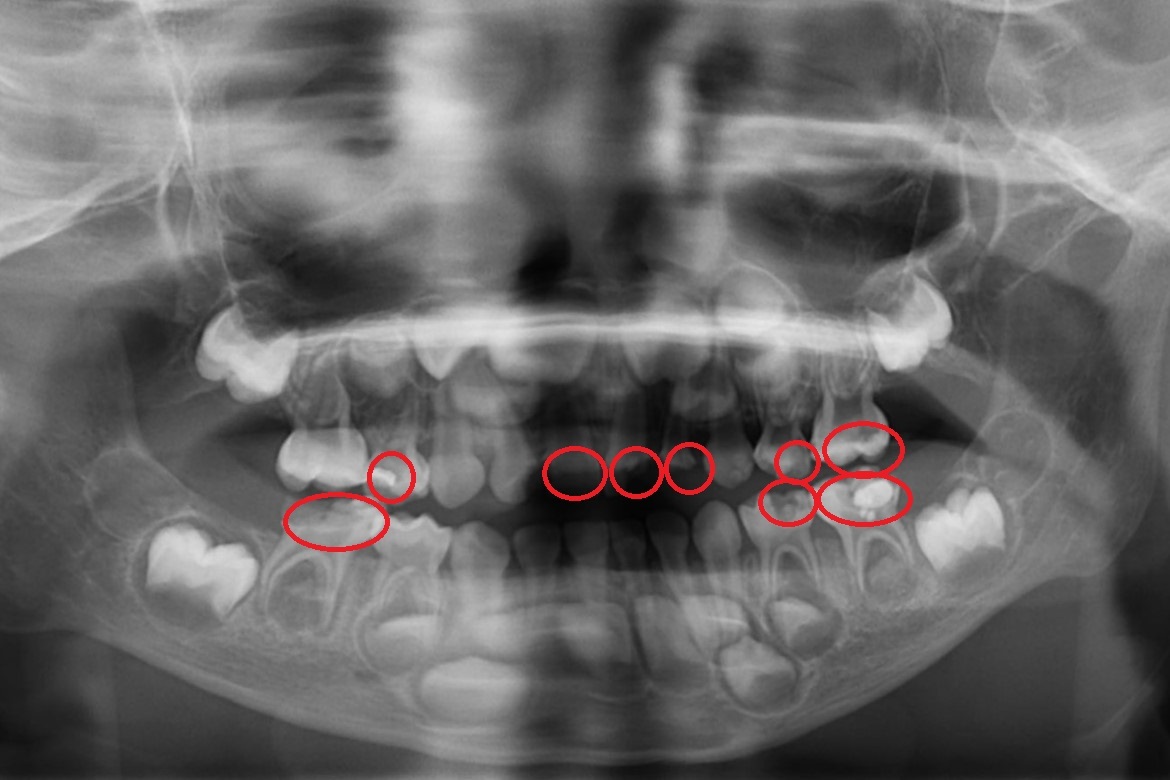

▲ X光看見孩子多顆蛀牙(紅圈處均是蛀牙處)。(圖/台北慈濟)